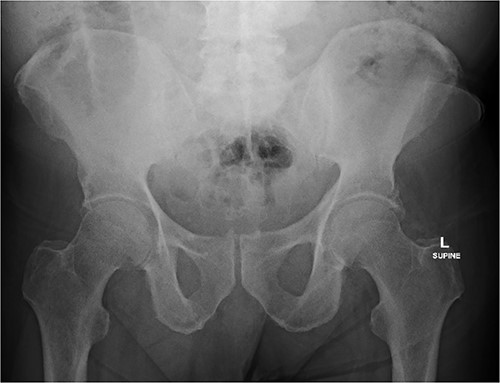

An 80 year old male presented to the emergency department after accidentally swallowing his hearing aids. On presentation he was pain free, hemodynamically stable, and had a soft abdomen. He had a background of type-2 diabetes, rheumatoid arthritis and diverticulitis. The hearing aids were powered by lithium battery. X-ray found two foreign bodies in the left upper abdomen (Fig. 1). After assessment in the emergency department, he returned home to await their natural passage. One hearing aid was found in his stools the following day, but he represented three weeks later as the second hearing aid remained unaccounted for. He underwent repeat abdominal x-ray and CT, which found the hearing aid retained within a presumed distal duodenal diverticulum (Figs 2 and 3). He was booked a push enteroscopy the following day.

Abdominal X-ray identifying two hearing aids on day of initial presentation.